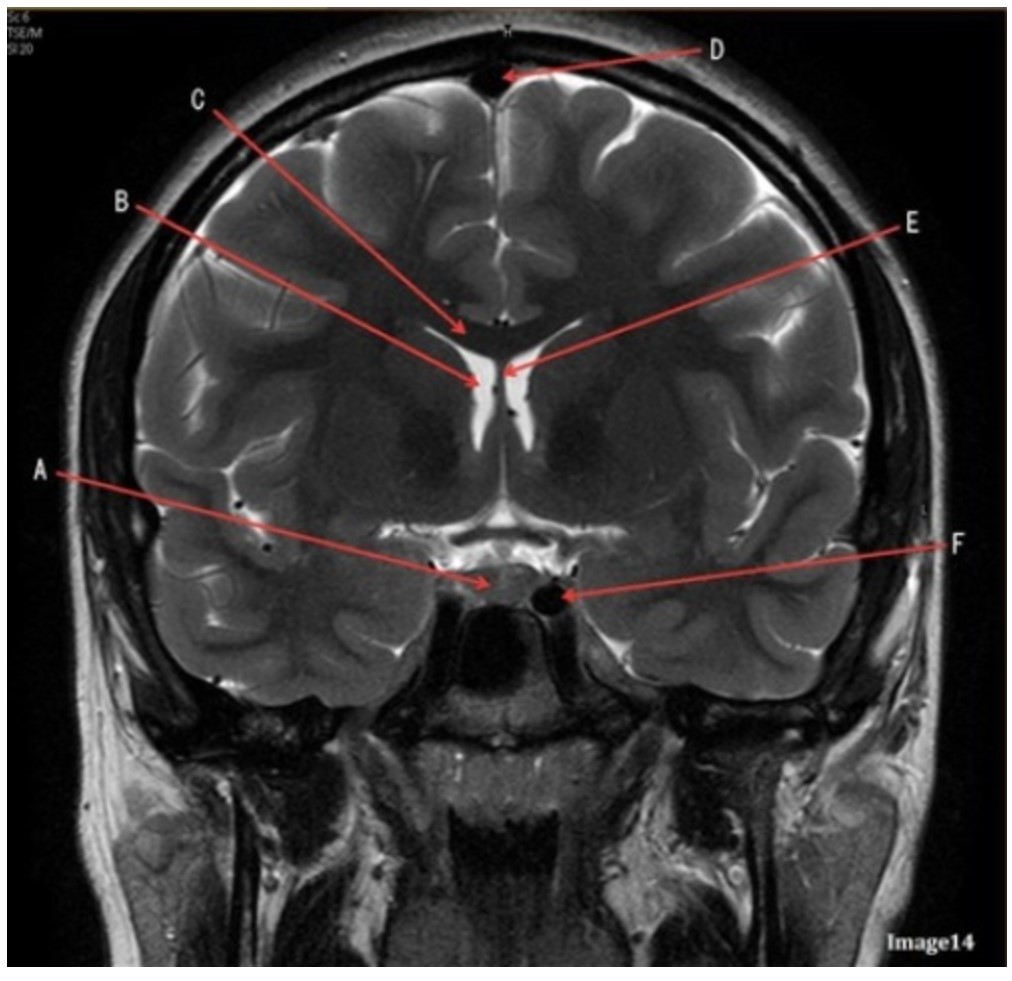

Letter F in Image 14 is pointing to:

A. Third ventricle

B. Pituitary gland

C. Hypothalamus

D. Internal carotid artery

Letter C in Image 14 is pointing to:

A. Corpus callosum

B. Third ventricle

C. Lateral ventricle

D. Pituitary gland

E. Fornix

Letter D in Image 14 is pointing to:

A. Tentorium

B. Sphenoid sinus

C. Frontal sinus

D. Sagittal sinus

E. Fornix

Letter B in Image 14 is pointing to:

A. Corpus callosum

B. Third ventricle

C. Lateral ventricle

D. Pituitary gland

E. Fornix

Letter E in Image 14 is pointing to:

A. Corpus callosum

B. Third ventricle

C. Lateral ventricle

D. Internal carotid artery

E. Fornix

Letter A in Image 14 is pointing to:

A. Corpus callosum

B. Third ventricle

C. Lateral ventricle

D. Pituitary gland

E. Fornix

Letter A in Image 14 is pointing to:

A. Corpus callosum

B. Third ventricle

C. Lateral ventricle

D. Pituitary gland

E. Fornix